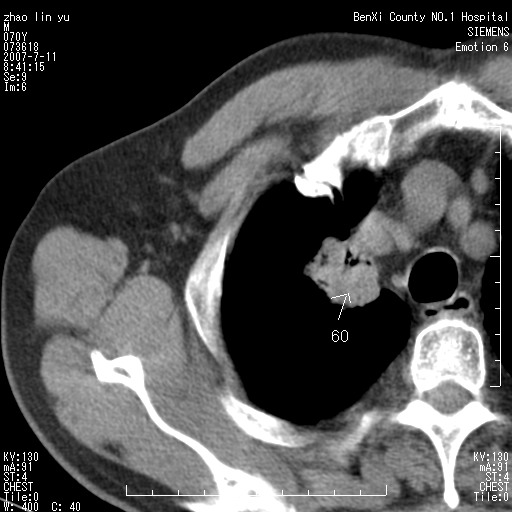

以下是引用王靖旗在2007-7-10 17:12:00的发言:[br] 男、70、咳嗽两个月,半年前换瓣手术,胸片未见异常,于昨天行x片发现右肺上野大片影,行ct扫描,这里是减薄图像,余肺正常。明天晚上会有增强扫描片,到时我会上传。[br][br] 冠状位请大家细看,应该是有意义的,[br][br] 请大家先看平扫发表意见。[br][br]

以下是引用zhangzhongshou在2007-7-10 21:43:00的发言:[br]右肺上叶周围型肺癌,以孤立型细支气管肺泡癌可能性大。